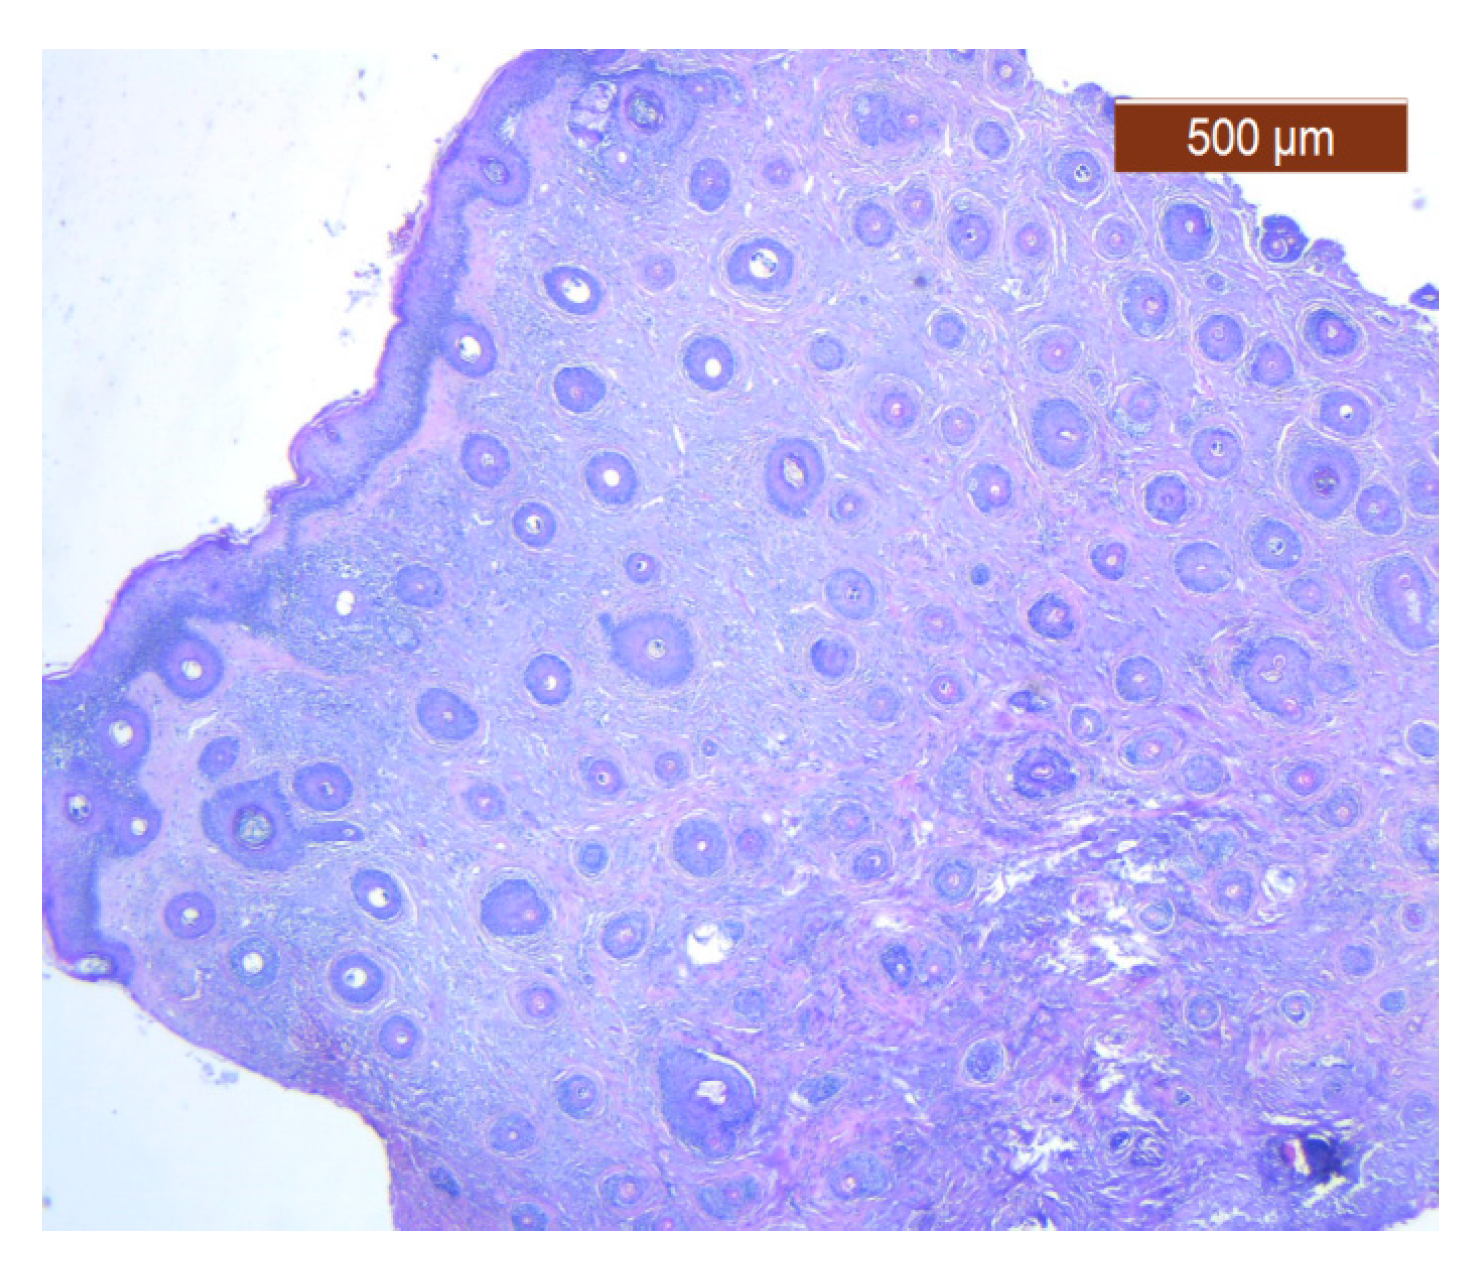

Figure 25. Muscle fibers in the SMAS layer (SMAS fibrous septum). SMAS fibrous septa are arranged perpendicular to the skin and enclose the univacuolar compartments of fat cells (HE ×5). Histological piece from biopsy of the lower lip.

Muscle fibers are also visible and take direct cutaneous insertion, perpendicular to the skin, crossing the superficial fascia (Figure 25 and Figure 26).

Through the usual staining, a very well-represented layer of collagen can be observed at the levels of both lips (Figure 23 and Figure 24).